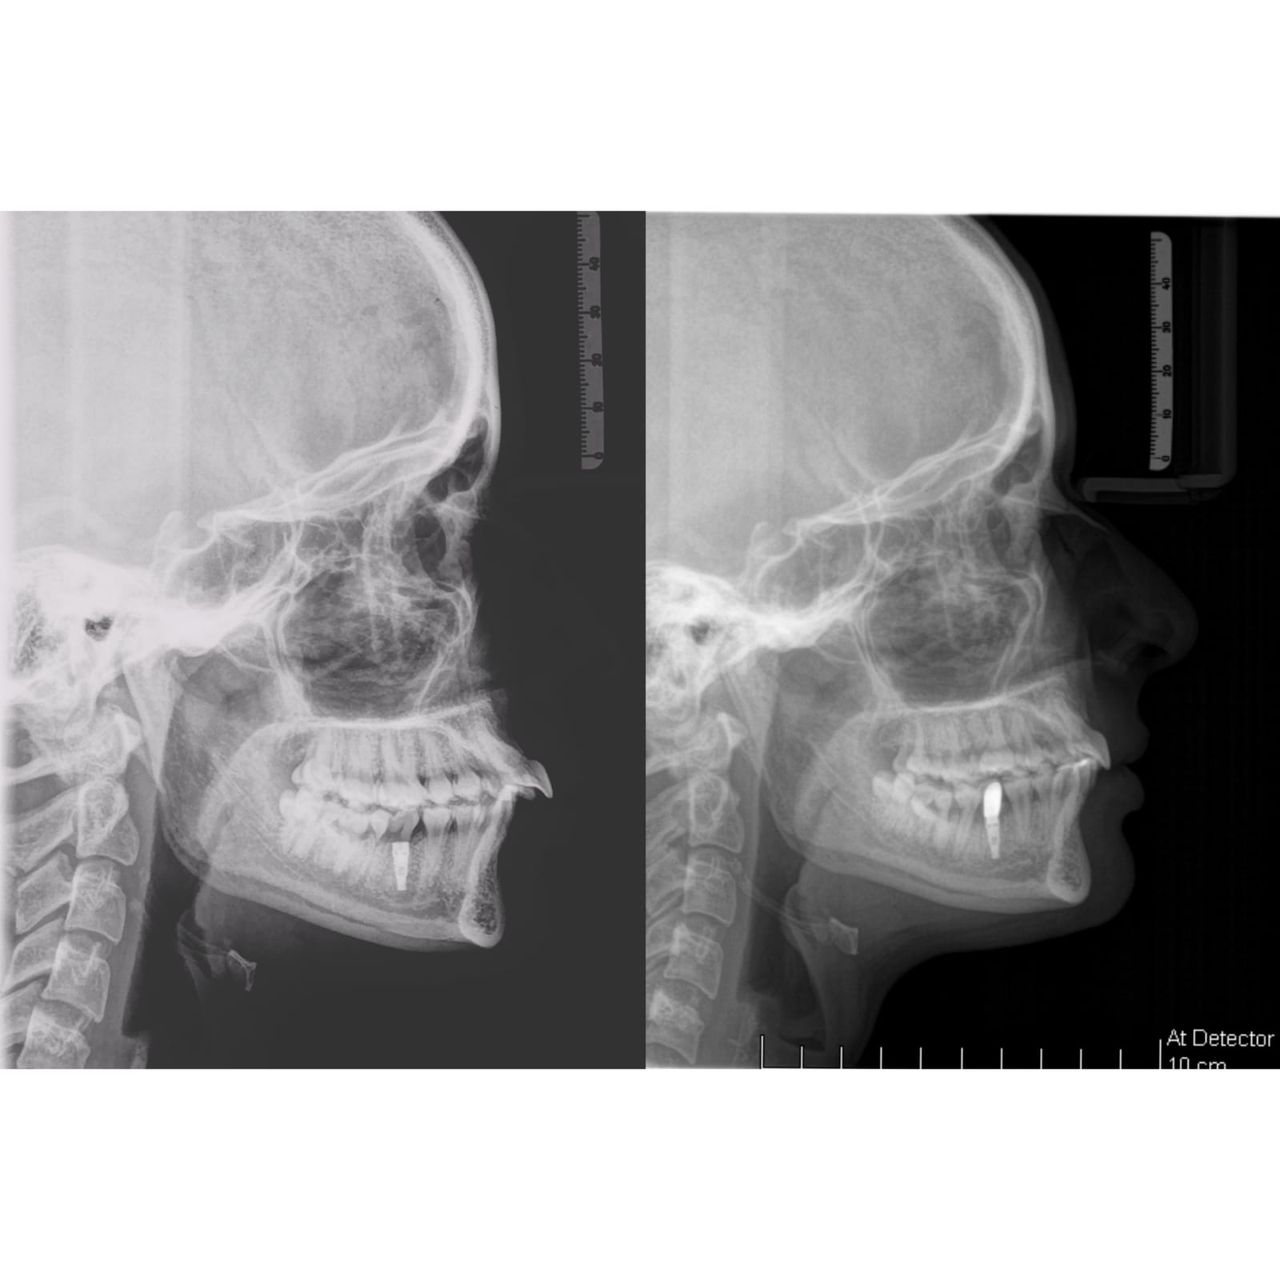

Il dottor Gianluca del Vecchio si occupa esclusivamente di ortognatodonzia, grazie anche alla collaborazione multidisciplinare di una équipe davvero entusiasmante e all’utilizzo di strumenti diagnostici e terapeutici all’avanguardia in ortognatodonzia. Particolare è la sua capacità di condurre i giovani pazienti ad affrontare, nella massima sicurezza emotiva e clinica, qualsiasi eventuale condizione di dolore derivante, ad esempio, da carie o da altre patologie, ma soprattutto di risolvere tutte quelle condizioni di “denti storti”, così spesso causa di disagio psicologico o di fenomeni deprecabili, quale il bullismo.

L’ortognatodonzia è la disciplina che si occupa dell’ortopedia delle ossa mascellari, interviene sulla crescita delle stesse modificando la posizione dei denti secondo quanto necessario. Così la pedodonzia, la seconda disciplina che si occupa, ma in modo esclusivo, dei bambini, affronta tutte le classiche patologie del cavo orale, quando i pazienti sono in età scolare.

Il suo percorso formativo, iniziato con laurea in odontoiatria con il massimo dei voti, è proseguito col costante obiettivo di raggiungere una eccellenza clinica, attraverso la specifica specializzazione, arricchita in seguito da diversi master in Europa e uno anche in America a Tucson, famoso centro ortodontico a livello mondiale.

Queste le ragioni che consentono di trattare le malocclusioni, sia dei bambini che degli adulti, con protocolli scientificamente validati come i più veloci, affidabili e confortevoli.

ho 28 anni e Ho una malocclusione dentale (2 classe scheletrica ) che non mi è stata mai curata in età evolutiva. lo studio dove sono andato mi ha proposto l'uso di invasigil per la durata di circa 1 anno , per un caso medio complesso come il mio è più adeguato un apparecchio fisso o vanno bene le mascherine trasparenti ?

guardi che potrà chiedere di visualizzare prima gli obiettivi del trattamento. E saranno abbastanza attendibili, mi creda